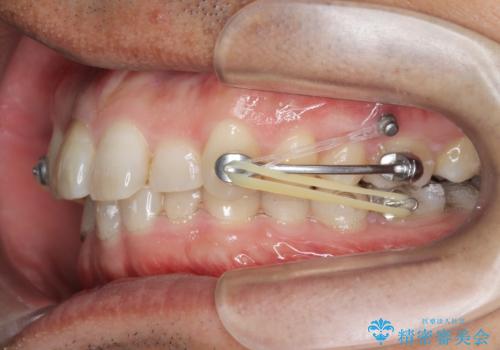

2級ディープバイト 遠心移動を伴うマウスピース矯正

・深い噛み合わせ(ディープバイト) ・2級性の咬合関係(上顎前突)・前歯のがたつき

以上のような歯並びの問題をマウスピース矯正インビザライン・カリエール・マイクロインプラント・部分ワイヤー矯正

を用いて改善していきます。

深い噛み合わせと上顎前突の状態を治すのに時間がかかりましたが、治療後は理想的で安定した咬合関係となりました。